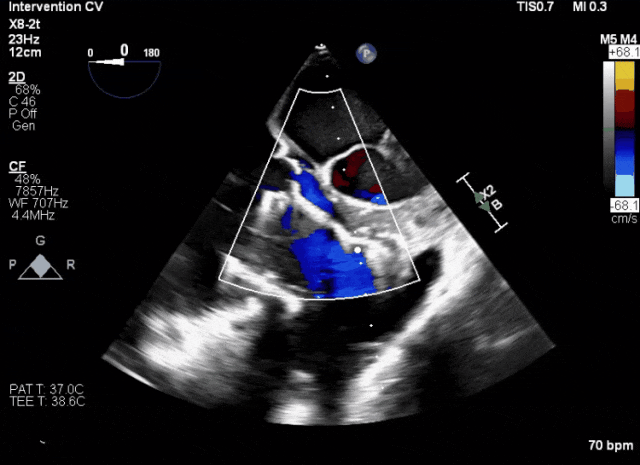

第二例患者手術難點

1、患者左心機械瓣術后,術中TEE成像有偽影干擾;2、三尖瓣重度反流,右心房、心室嚴重擴張致三尖瓣葉拴系,Gap:15.3mm,注意阻擋件抓取瓣葉操作。

術中TEE成像困難,偽影干擾

術后DSA、超聲顯示人工瓣膜穩定性良好,瓣葉啟閉正常,無瓣周漏